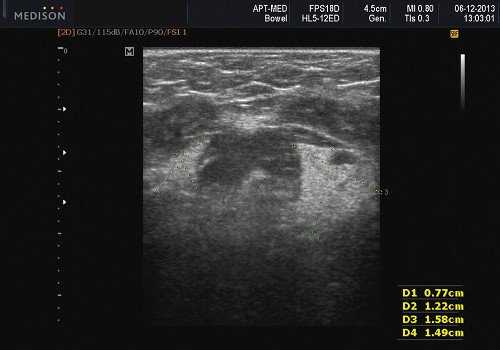

- обструктивные сиаладениты, развивающиеся при затруднении оттока слюны при обструкции выводного протока камнем (рис. 5-7) или сгустившимся секретом, а также вследствие рубцового стеноза протока. По распространенности процесса различают очаговый, диффузный сиаладениты и сиалодохит - воспаление выводного протока. Течение процесса может быть острым и хроническим;

Рис. 5. Камень протока поднижнечелюстной слюнной железы.

Рис. 6. Камень в паренхиме поднижнечелюстной слюнной железы.

Рис. 7. Камень в протоке поднижнечелюстной слюнной железы.